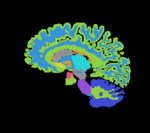

Co-registration of two anatomic brain atlases for merging of structure labels

this is the fixed reference image. All images are aligned into this space this is the fixed target, a label-map in the same space as the fixed reference. The registration target is derived from this image lleft this is the moving image, but the transform is calculated by matching surfaces derived from the labelmaps this is the moving image to which the calculated transform is applied. The model surfaces used to calculate the transform are derived from this image

Target Atlas T1 Target Atlas Labelmap Moving Atlas T1 Moving Atlas Labelmap

This is an example of inter-subject registration via surface matching. The structures of interest are a small subset of the entire image, hence registration is not driven by image intensities but rather two model surfaces derived from the labelmaps.